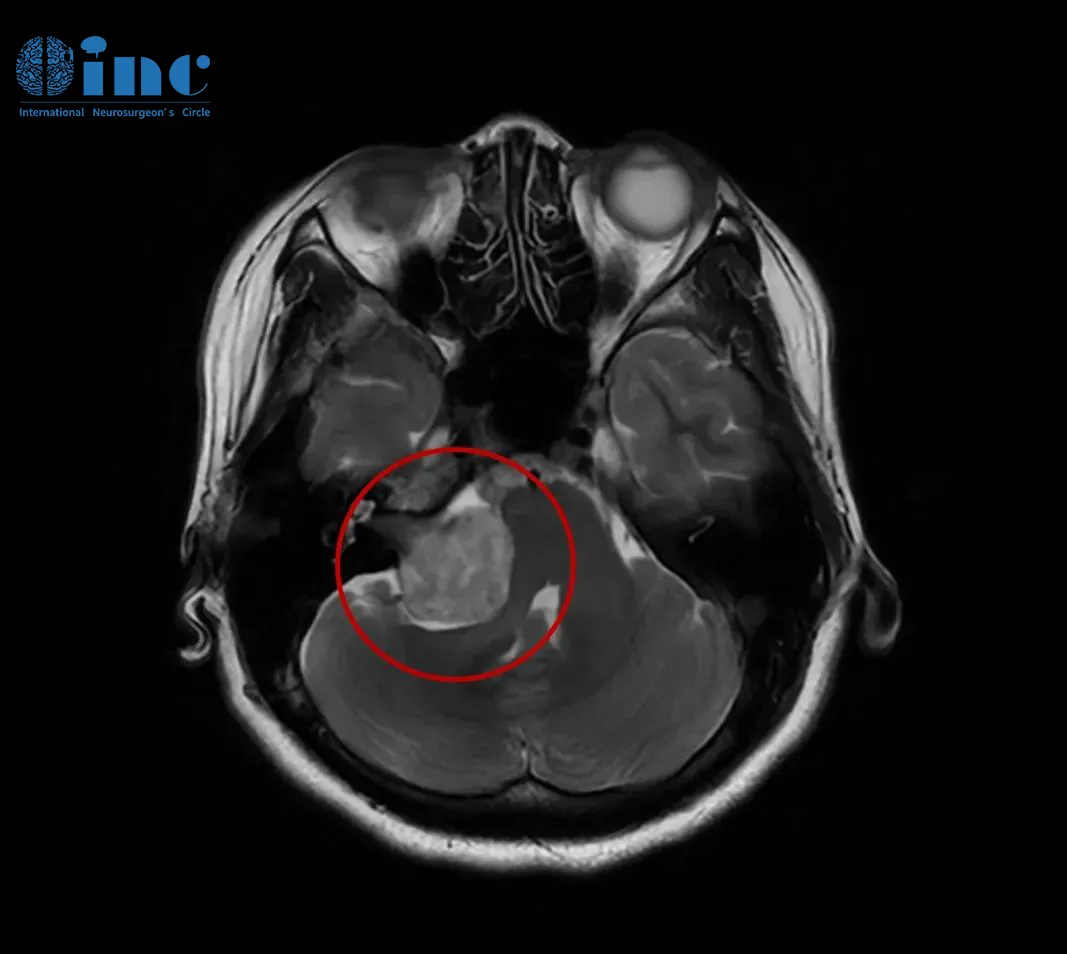

住院治疗两周后,他的听力虽暂时恢复至20-30分贝,但头颅增强MRI检查发现了真正元凶——右侧听神经瘤,且肿瘤大部分深嵌在内听道内。

这个位置的肿瘤与面听神经紧密缠绕,手术极易损伤神经导致永久性面瘫——这对需要频繁站在讲台的高老师来说,是职业和尊严的双重打击。

在保守观察期间,肿瘤再次引发突聋,并新增走路眩晕症状。抱着“保面、全切、保听”的诉求,他联系上巴教授。2022年春,巴教授采用“内听道磨除术+膜内切除术”,成功切除肿瘤并完好保留面听神经功能。